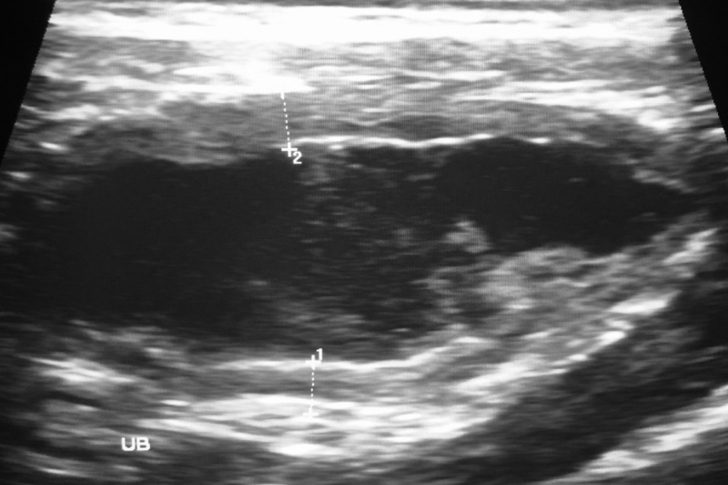

Die Tiermedizinerin hatte von Anfang an die Vermutung, dass das Königstier einen Fremdkörper verschluckt hatte. Ihre Hypothese wurde durch die Ultraschallbilder bestätigt, welche eine Blockade am Mageneingang zeigten. Diese Verstopfung verhinderte, dass der Fremdkörper natürlich verdaut und ausgeschieden werden konnte. Infolgedessen litt der Löwe unter unerträglichen Schmerzen, während sein Bauch sich weiterhin gefährlich ausdehnte und so zu einer immer größer werdenden Gefahr für das Tier wurde. Nun schien es nur einen einzigen Weg zu geben, um dem König der Tiere zu helfen. Die Ärztin war entschlossen und hoffte inständig, dass ihr Vorhaben von Erfolg gekrönt sein würde. Was genau plante sie nun? Und konnte sie den Löwen tatsächlich retten?